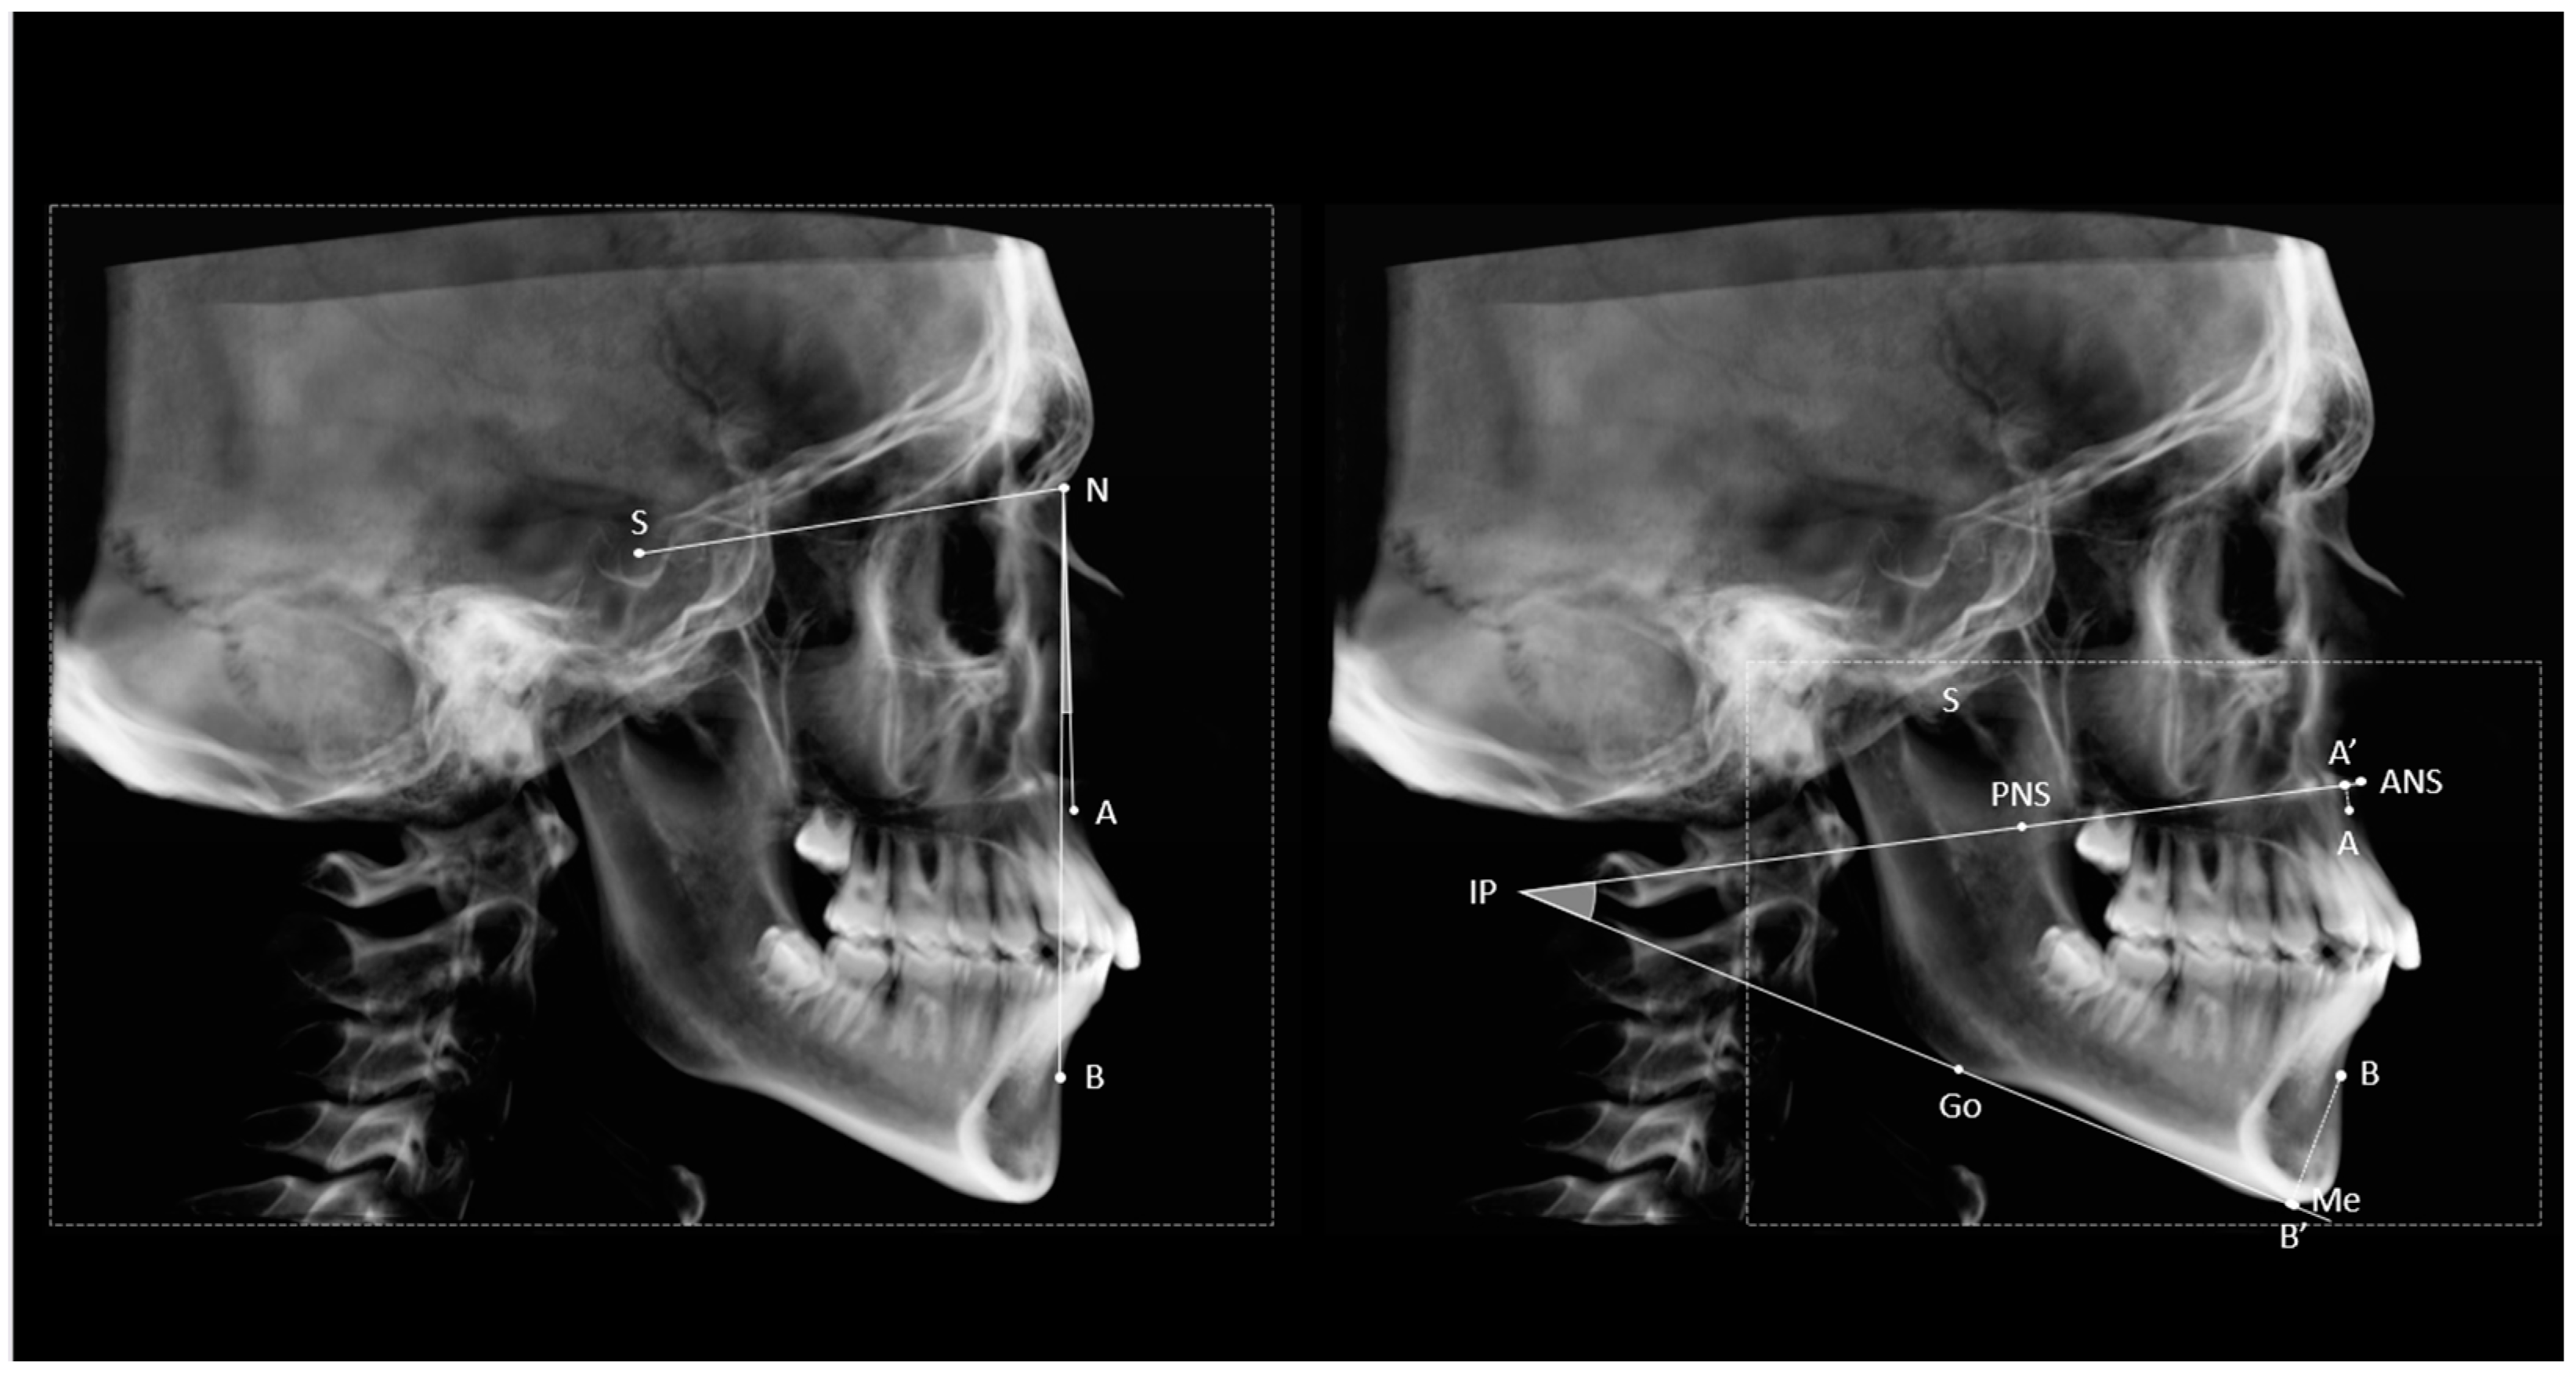

Figure 1 shows a graphic representation of the construction methods for ANB and ABwise. The projections of points A and B onto the BL line (A’) and the mandibular plane (B’) were then constructed. Finally, the distances from A’ and B’ to the IP were used to calculate the ABwise by the following formula: